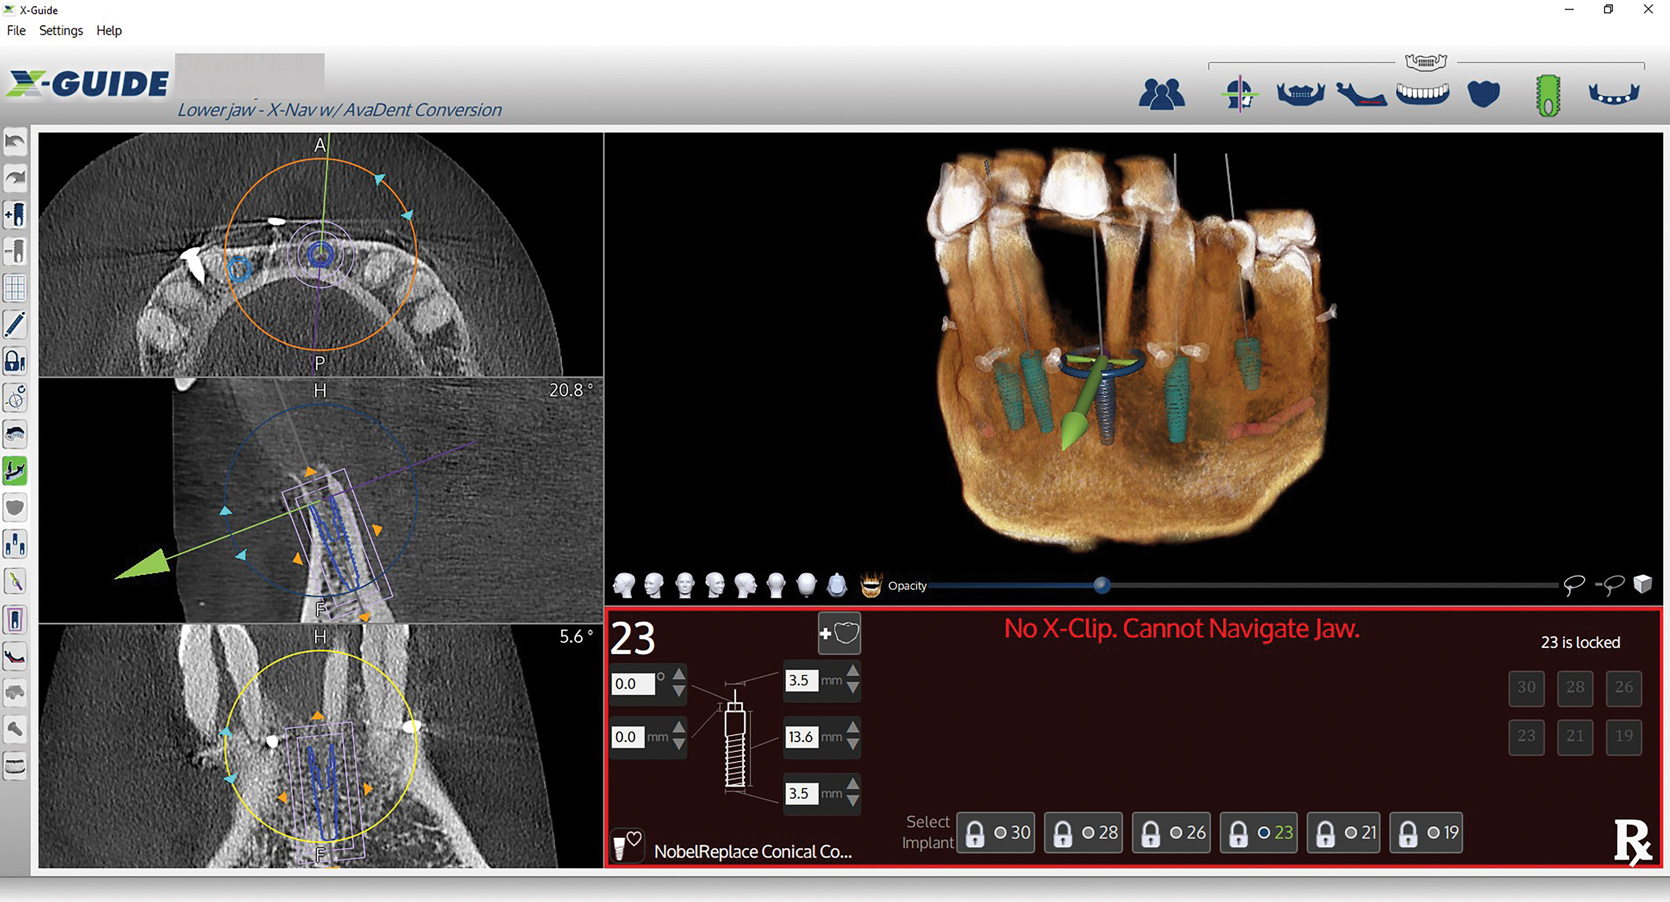

Figure 5: Screen capture shows the exported virtual implant plan ready for dynamic navigation surgery.

Figure 5